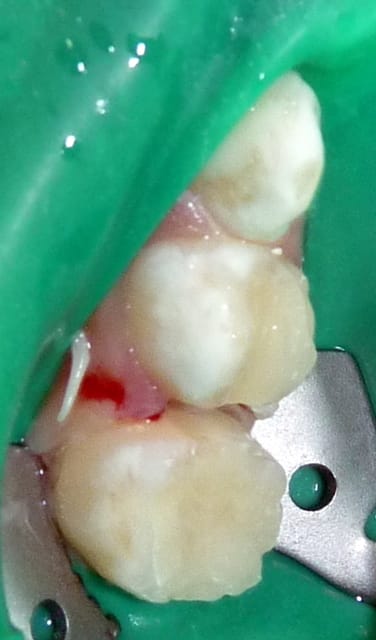

20/07/11 : secteur II.

Hygiène toujours très bonne sauf en postérieur des secteurs II/II car 75 très douloureuse. (Je ne me suis rendu compte qu'à la fin de la séance de la saleté en vestibulaire de 65: heureusement nettoyée avant scellement CPP !).

65 : Pulpo. Moignon CVI. CPP.

Fluoration.